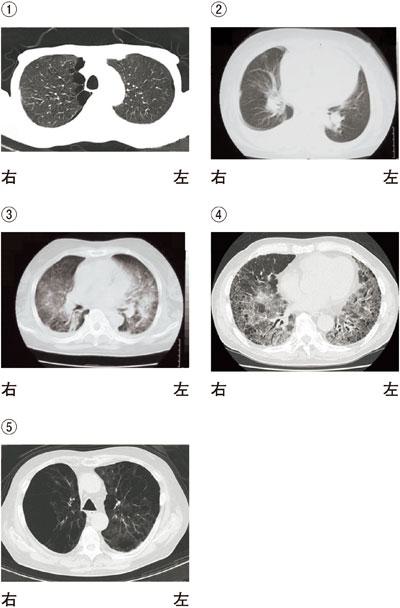

次の文を読み、問題17、問題18の問いに答えよ。65歳の男性。間質性肺炎。労作時呼吸困難、咳を主訴に来院した。3年前から歩行時の呼吸困難が増悪した。1か月前から咳、労作時の呼吸困難の悪化を認め入院となった。入院時、心電図は洞調律。血液検査ではCRP 3.1 mg/dL(基準値:0.3 mg/dL未満)、KL-6 790 U/mL(基準値500 U/mL未満)であった。理学療法評価では、mMRC息切れスケールはグレード3。筋力はMMT上下肢4、6分間歩行テストは200 mであった。胸部CTを示す。この患者の胸部CTとして最も可能性が高いのはどれか。

1

①

2

②

3

③

4

④

5

⑤